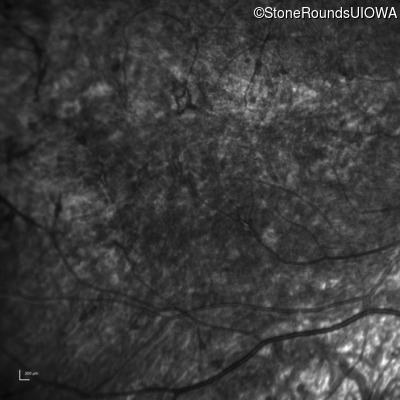

Infrared Fundus Photograph - Left - 5/180

Exemplar